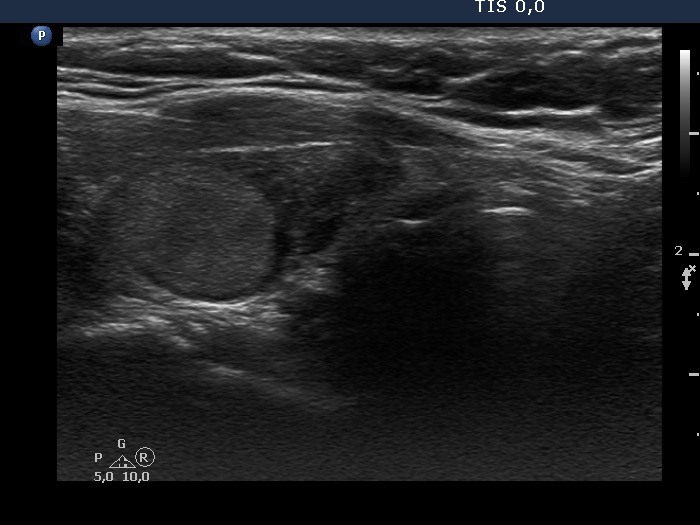

Consecutive patients with the final diagnosis of Hashimoto's thyroiditis - case 7 (851) (ultrasonographic picture 5)

Left lobe, longitudinal scan. The lower part of the lobe is hypoechogenic corresponding to the underlying Hashimoto's thyroiditis.